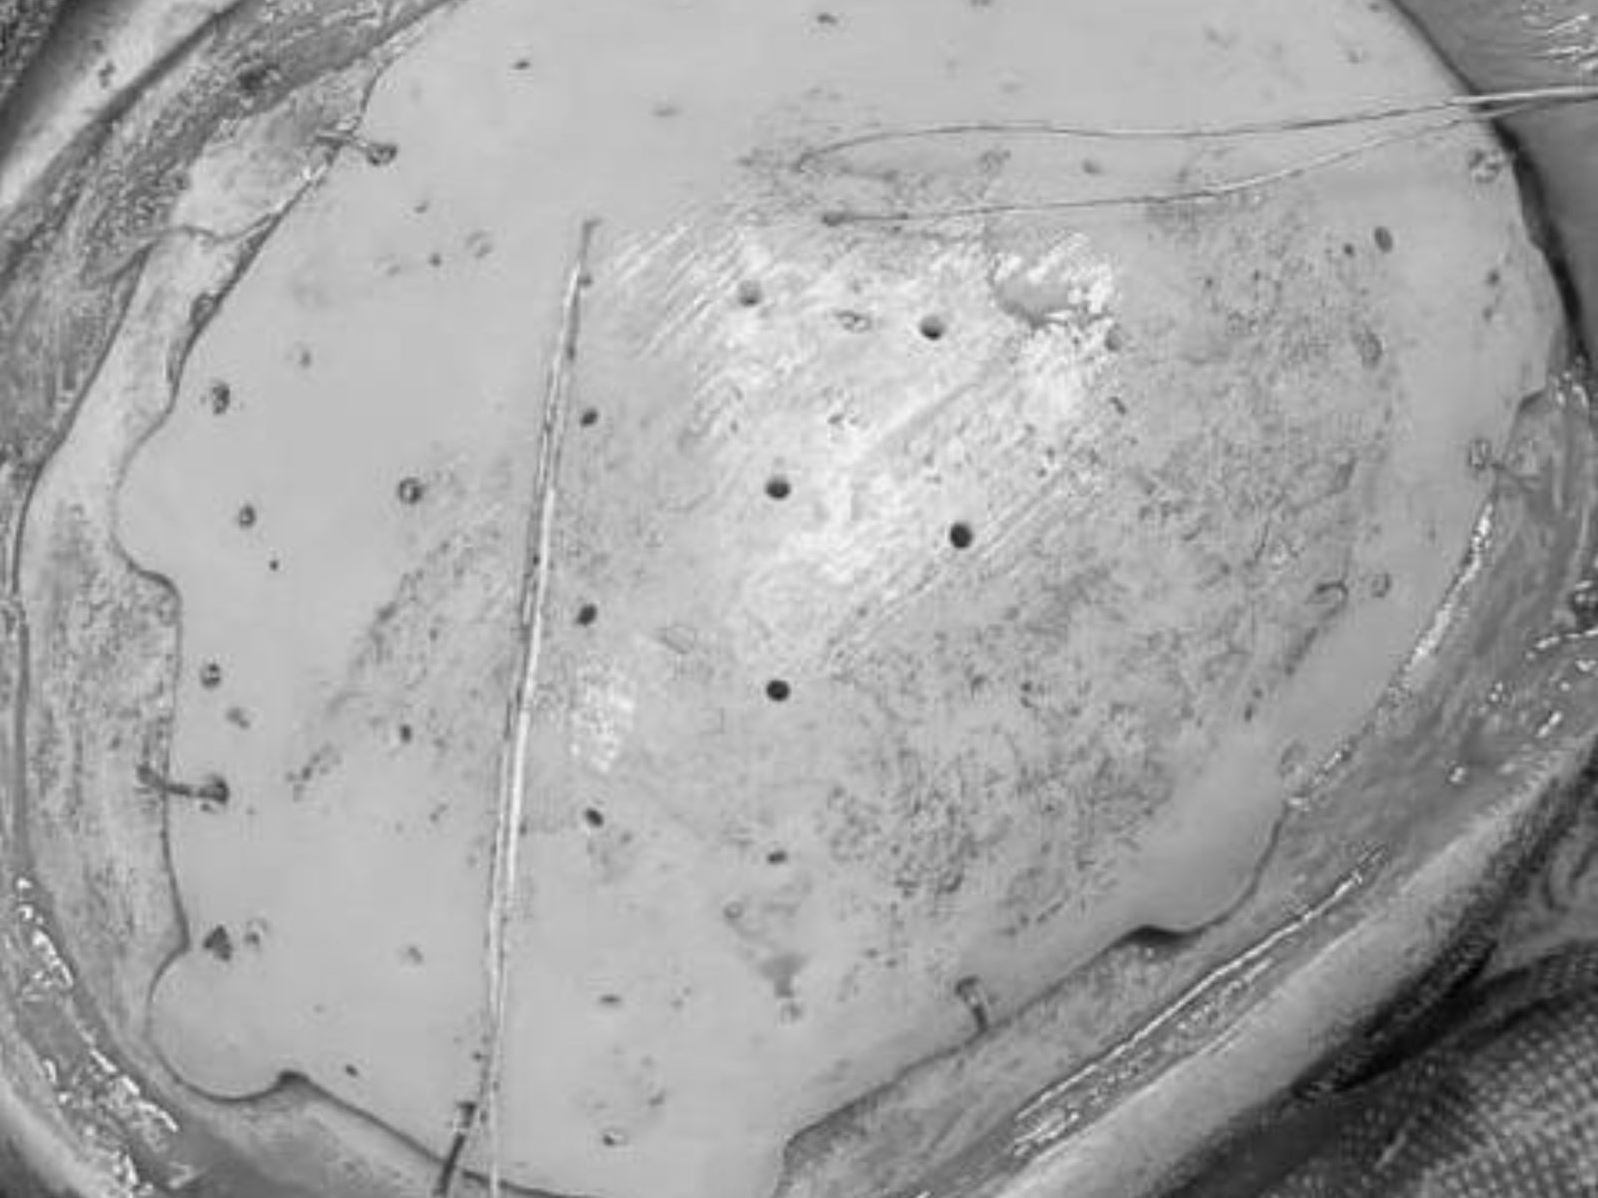

В Оренбурге хирурги восстановили юноше череп с помощью индивидуального импланта